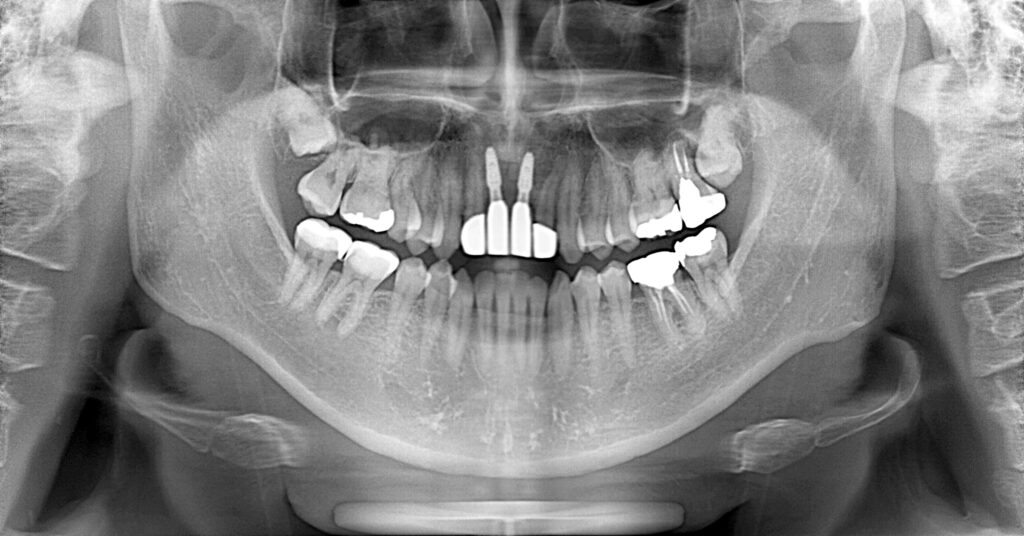

症例一覧 インプラント症例3 2024.11.25 治療内容インプラント主訴前歯部折れたのでインプラント治療を行いたい費用¥1259,500(2本)治療期間治療期間 7ヶ月 インビザライン症例1 前の記事 インプラント症例2 次の記事